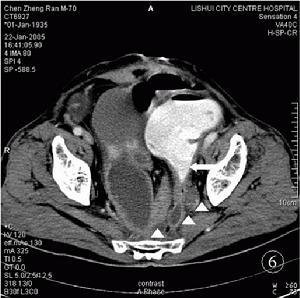

疾病名称粘连性肠梗阻疾病分类普通外科 疾病预防预防及时、正确治疗腹腔炎症对防止粘连的发生有重要意义。疾病描述粘连性肠梗阻是肠粘连或腹腔内粘连带所致的肠梗阻,较为常见,其发生率占各类肠梗阻的20%一40%。